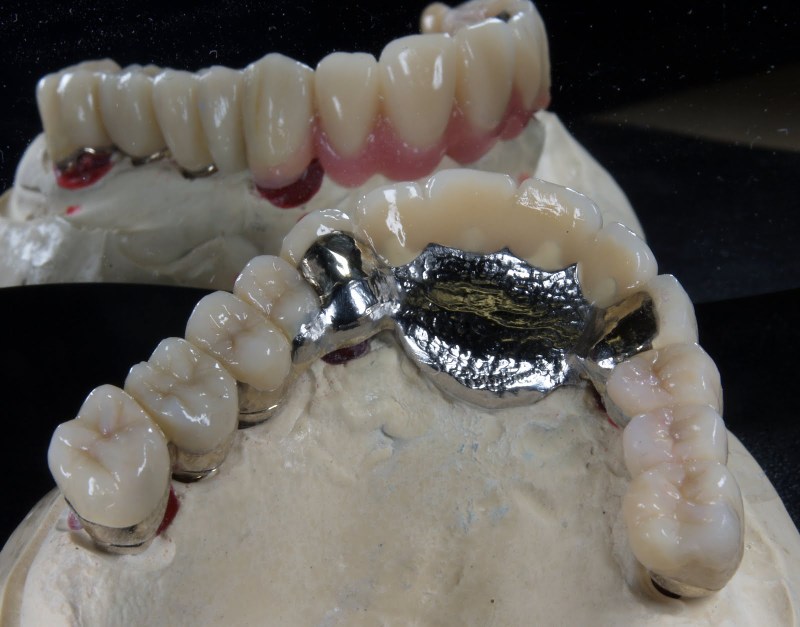

Keramik auf Metall